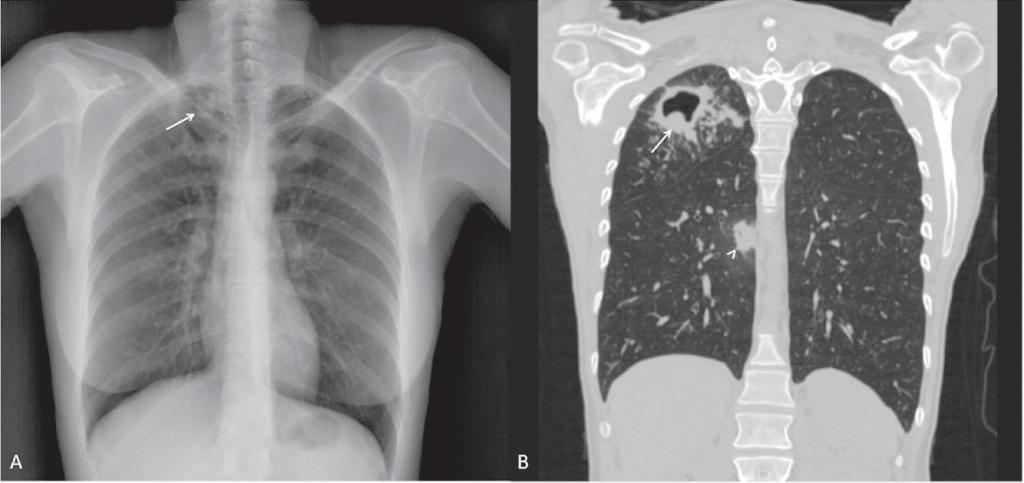

Первичный туберкулез

Эта форма туберкулеза поражает детей или пожилых людей. Выделяют три подтипа:

• туберкулез невыясненной локализации;

• туберкулез внутригрудных лимфатических узлов;

• первичный туберкулезный комплекс.

При первом подтипе, несмотря на наличие симптоматики, изменения в легких на рентгене выявить не удается. Поэтому необходимо дальнейшее обследование для выяснения локализации патологического процесса.

При втором подтипе поражаются лимфатические узлы средостения: парабронхиальные, парааортальные, паратрахеальные. То, как выглядит туберкулез на снимке, напрямую зависит от локализации пораженных лимфатических узлов:

• характерно расширение корня легкого с размытыми краями;

• возможно наличие неоднородности полей легкого.

Первичный туберкулезный комплекс определяется на рентгене при наличии таких трех признаков:

• «дорожка», которая идет к корню легкого (лимфангит);

• расширение корня, связанное с воспалением лимфатического узла (лимфаденит);

• очаг высокой плотности в ткани легкого, возникающий при отложении солей кальция (очаг Гона).